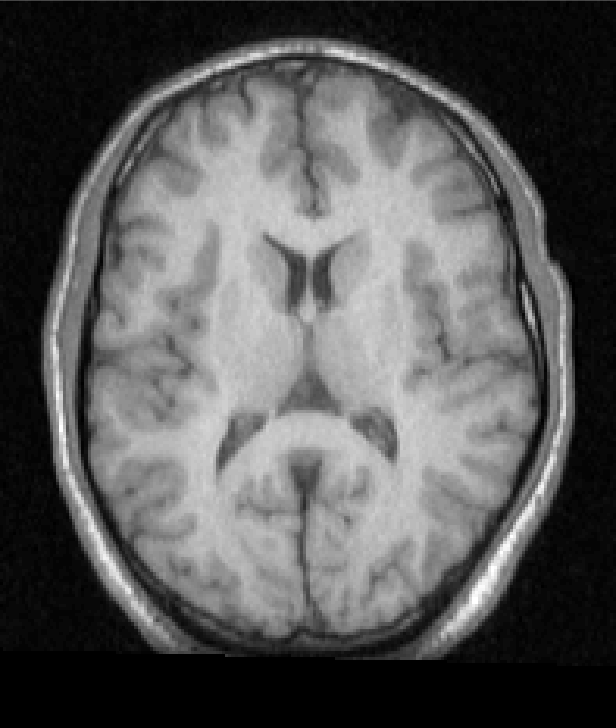

Fig. 1 shows example images from each dataset to illustrate image variability. IBSR and LPBA40 contain images from normal subjects and include large portions of the neck; BRATS has very low out-of-plane resolution; and the TBI dataset contains large pathologies and abnormal skulls.

Refer to caption

Figure 1: Illustration of image appearance variability on a selection of images from each (evaluation) database. From top to bottom: IBSR, LPBA40, BRATS and TBI.